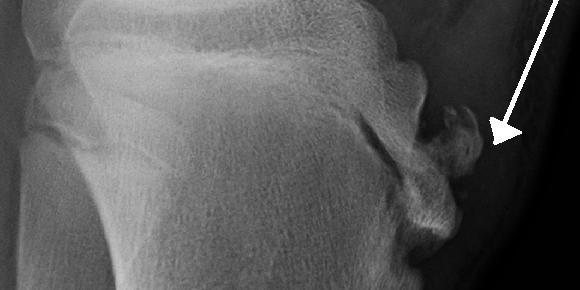

It occurs when the patellar tendon (the tendon below the kneecap) pulls on the tibial tuberosity — the bony bump on the upper shin — during rapid growth phases.

The repeated stress causes irritation, inflammation, and sometimes a visible bump or swelling below the knee.